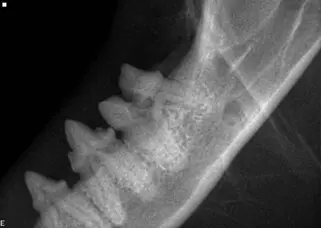

Tooth resorption (TR) on the left mandibular 1st molar tooth. This was not noticed by the naked eye.